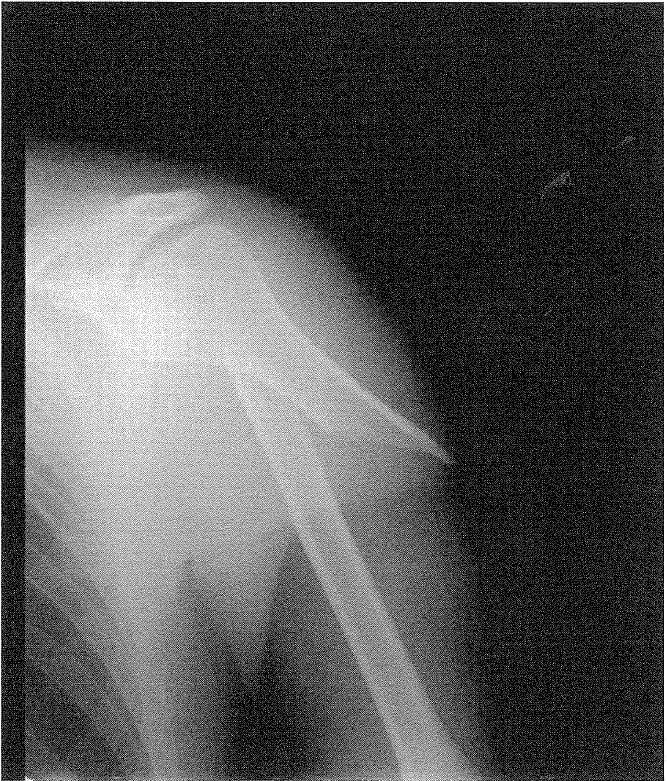

・単純エックス線写真:上腕骨骨幹部骨折の疑い

1.〇 正しい。肩関節外転位:手関節伸展位がまず行うべき固定肢位の組合せである。本症例は、橈骨神経麻痺を伴う上腕骨骨幹部骨折が疑われる。

・肩関節外転位(70~80°):三角筋・橈骨神経の緊張を緩和し、さらなるズレを防ぐことができる。

・手関節伸展位(背屈位):橈骨神経麻痺による下垂手を防ぎ、拘縮予防につながる。

〇橈骨神経麻痺とは、母指背側の感覚障害と上腕三頭筋・腕橈骨筋・長、短橈側手根伸筋、総指伸筋などの伸筋群の麻痺(下垂手)を認める。感覚領域は、親指から中指の背側、手背の橈側(親指側)、前腕の背側、上腕の背側と外側である。